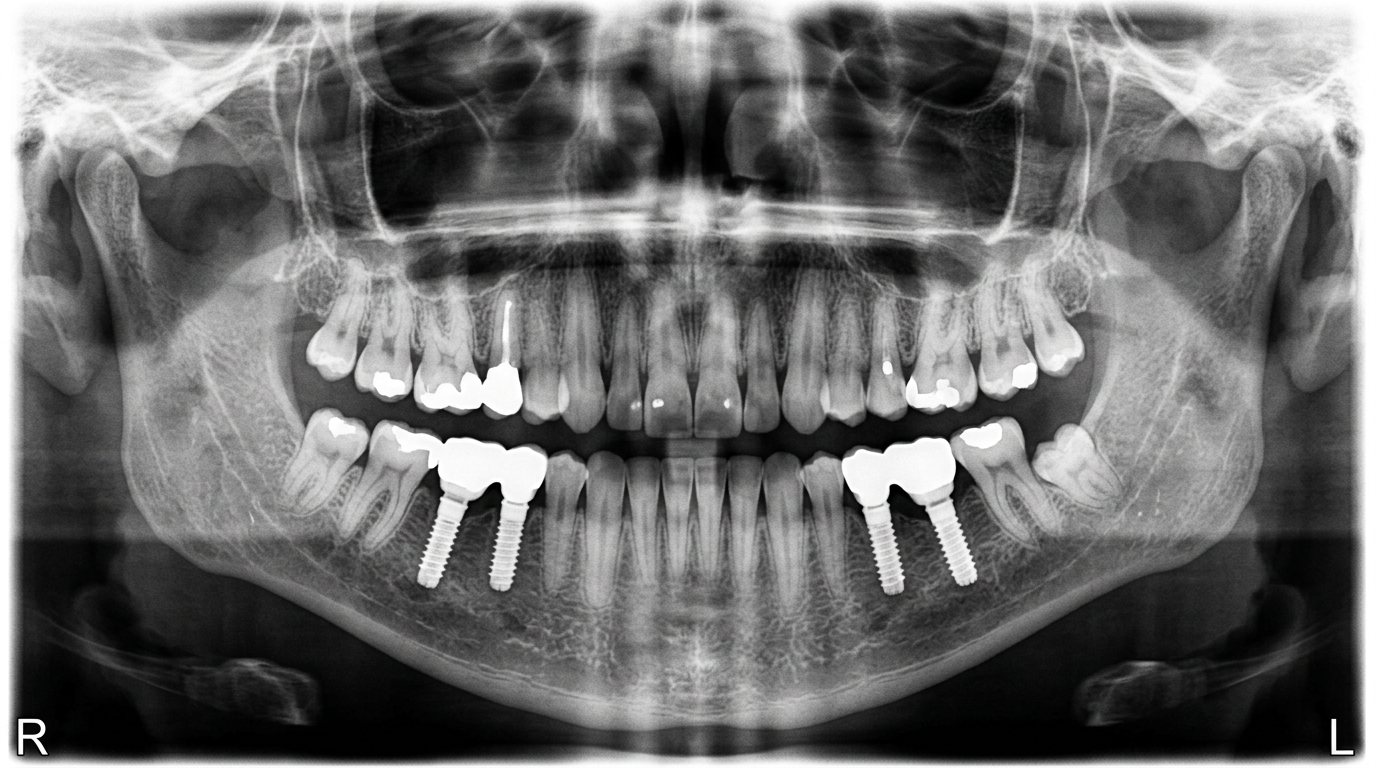

파노라마 X-ray

BEFORE하악 사랑니 4개 동시 발치 (수평매복 포함) 파노라마 비포